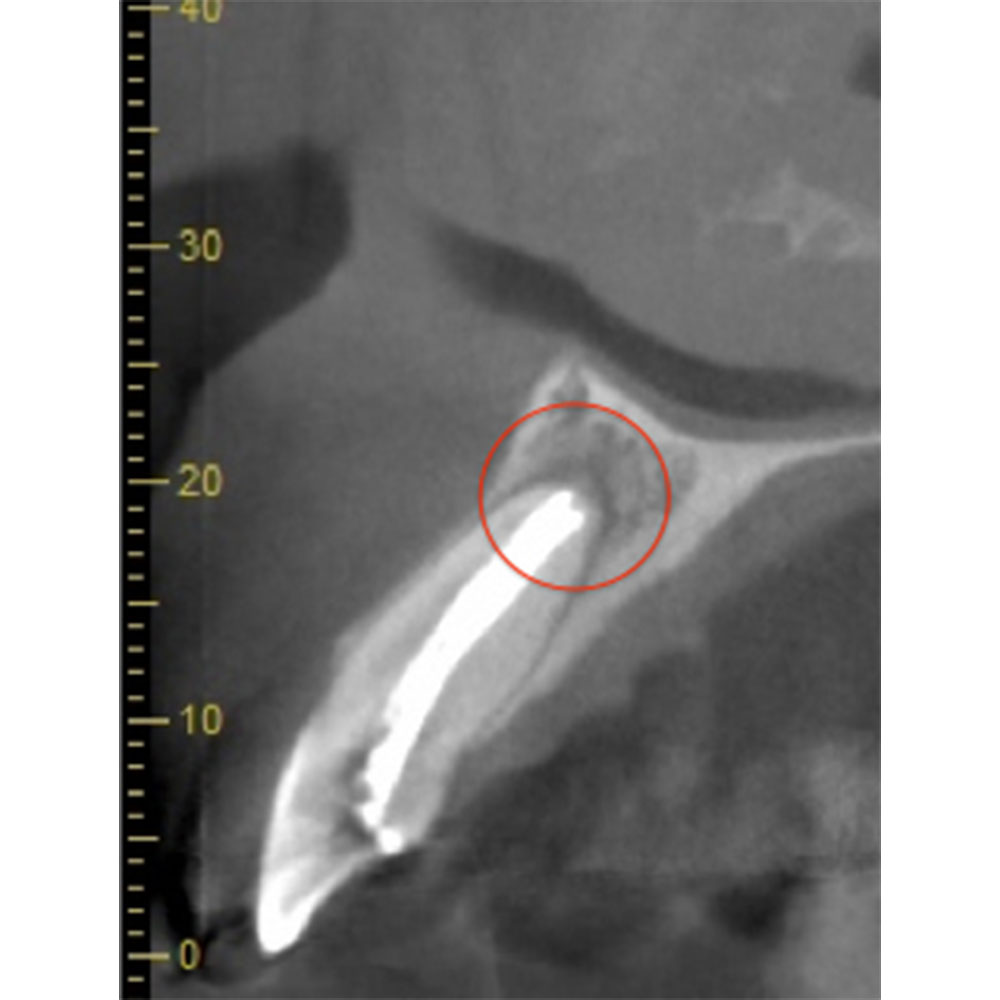

| 根の中にお薬を充填した後のCT画像。やはり根の先に黒い影があるのがわかります。 |

| 根の先の黒い影は消失しました。 | 術後6ヶ月のCT画像です。こちらでも、根の先に黒い影は見当たらないです。 |

患歯を見極めるためと、状態の悪さをみるため、CTを撮影しました。治療前では上顎洞への大きな炎症が見られます。また、上顎洞底線も無くなっています。また左上の前から4番目の歯の根尖周囲にも透過像が見られます。5番目の歯に関しては根尖が鋭利になっており、根尖性歯周炎によって吸収されたことがわかります。ですので、まず第一の患歯は5番目の歯であるとしました。

治療後3ヶ月経つと上顎洞への炎症も無くなっています。また、上顎洞底線もきれいにみえます。4番目の歯の根尖周囲の透過像もなくなりました。5番目の根尖にまだ透過像がありますが、臨床的症状がないことから、治癒傾向にあるものと判断しました。